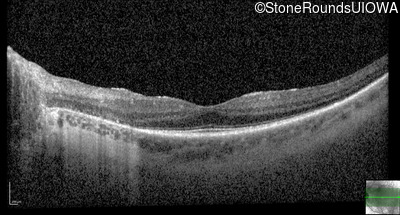

Optical Coherence Tomography - Right - 20/40 -1

Exemplar / OCT Stack